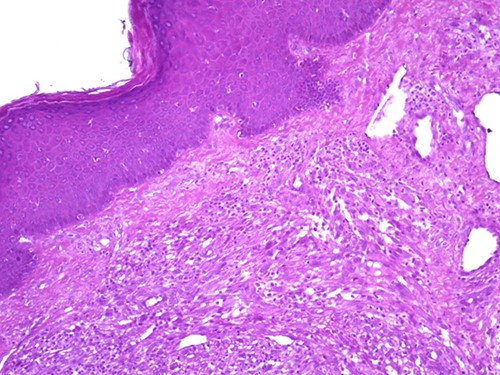

A 42-year-old man with no clinical history presented with a non-ulcerated polypoid skin nodule of the front side of the chest wall, which had grown over a period of 6 months, measuring 1,8 × 1,5 cm (Fig. 1). The lesion was removed completely with tumor-free margins of 0,5 cm. Microscopically, the tumor was composed of a diffuse infiltrate of polygonal cells with abundant granular cytoplasm and vesicular nuclei (Figs 2 and 3). There was no atypia or necrosis. The average mitotic count was one to two per 10 high-power field. Immunohistochemistry showed positive expression for CD10, CD68 and ALK with negative staining for CK AE1/AE3, CD34, S100 and HMB45 (Figs 4 and 5). No recurrence was noted during follow-up of 6 months.

Dermal nonneural granular cell tumor presenting as a non-ulcerated polypoid skin nodule of the front side of the chest wall.